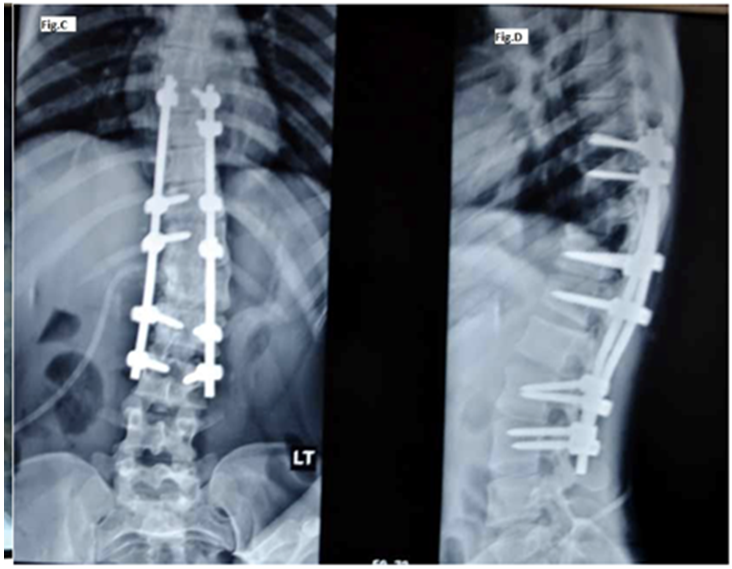

Figure 2 PA and lateral radiographs of the same patient showing curve correction by selective spinal instrument with pedicle screws and rods.

The medical record revealed that all operations were done by a single spinal deformity correction surgeon using an identical technique. The operative notes indicated that all procedures were done in a prone position on the radiolucent table under controlled hypotensive anaesthesia. Somato sensory evoked potential and motor evoked potential(Intraoperative neuromonitoring)was used during the procedure. A midline incision was given over the spinous processes and subperiosteal dissection was done to expose the pedicles and transverse processes. All pedicle screws were passed by freehand technique and confirmed by intraoperative imaging. Polynices Spine System was used for instrumentation. Two levels each at the upper and lower end of fusion mass were instrumented bilaterally followed by instrumentation of one vertebra at the apex on the convex side and two adjacent vertebrae on the concave side. Facet joints and spinouts process was excised to provide raw area as well as an autogenous bone graft for spinal fusion. Upper-end vertebrae (UEV) were neutral and lower end vertebrae (LEV) were stable. However, a final decision was dependent on the intraoperative alignment of the disc below LEV. If a level disc was achieved instrumentation was stopped at LEV otherwise instrumentation was extended to one level below. Pre-contoured rob was placed to correct the coronal and sagittal balance. The residual deformity was corrected by distracting the concave side and compressing the convex side of the deformity. The rotational deformity was corrected by the rod derotation method (Figure 1 & 2). The single drain was placed in a sub-fascial area which was removed on the first postoperative day and the patient was mobilized.